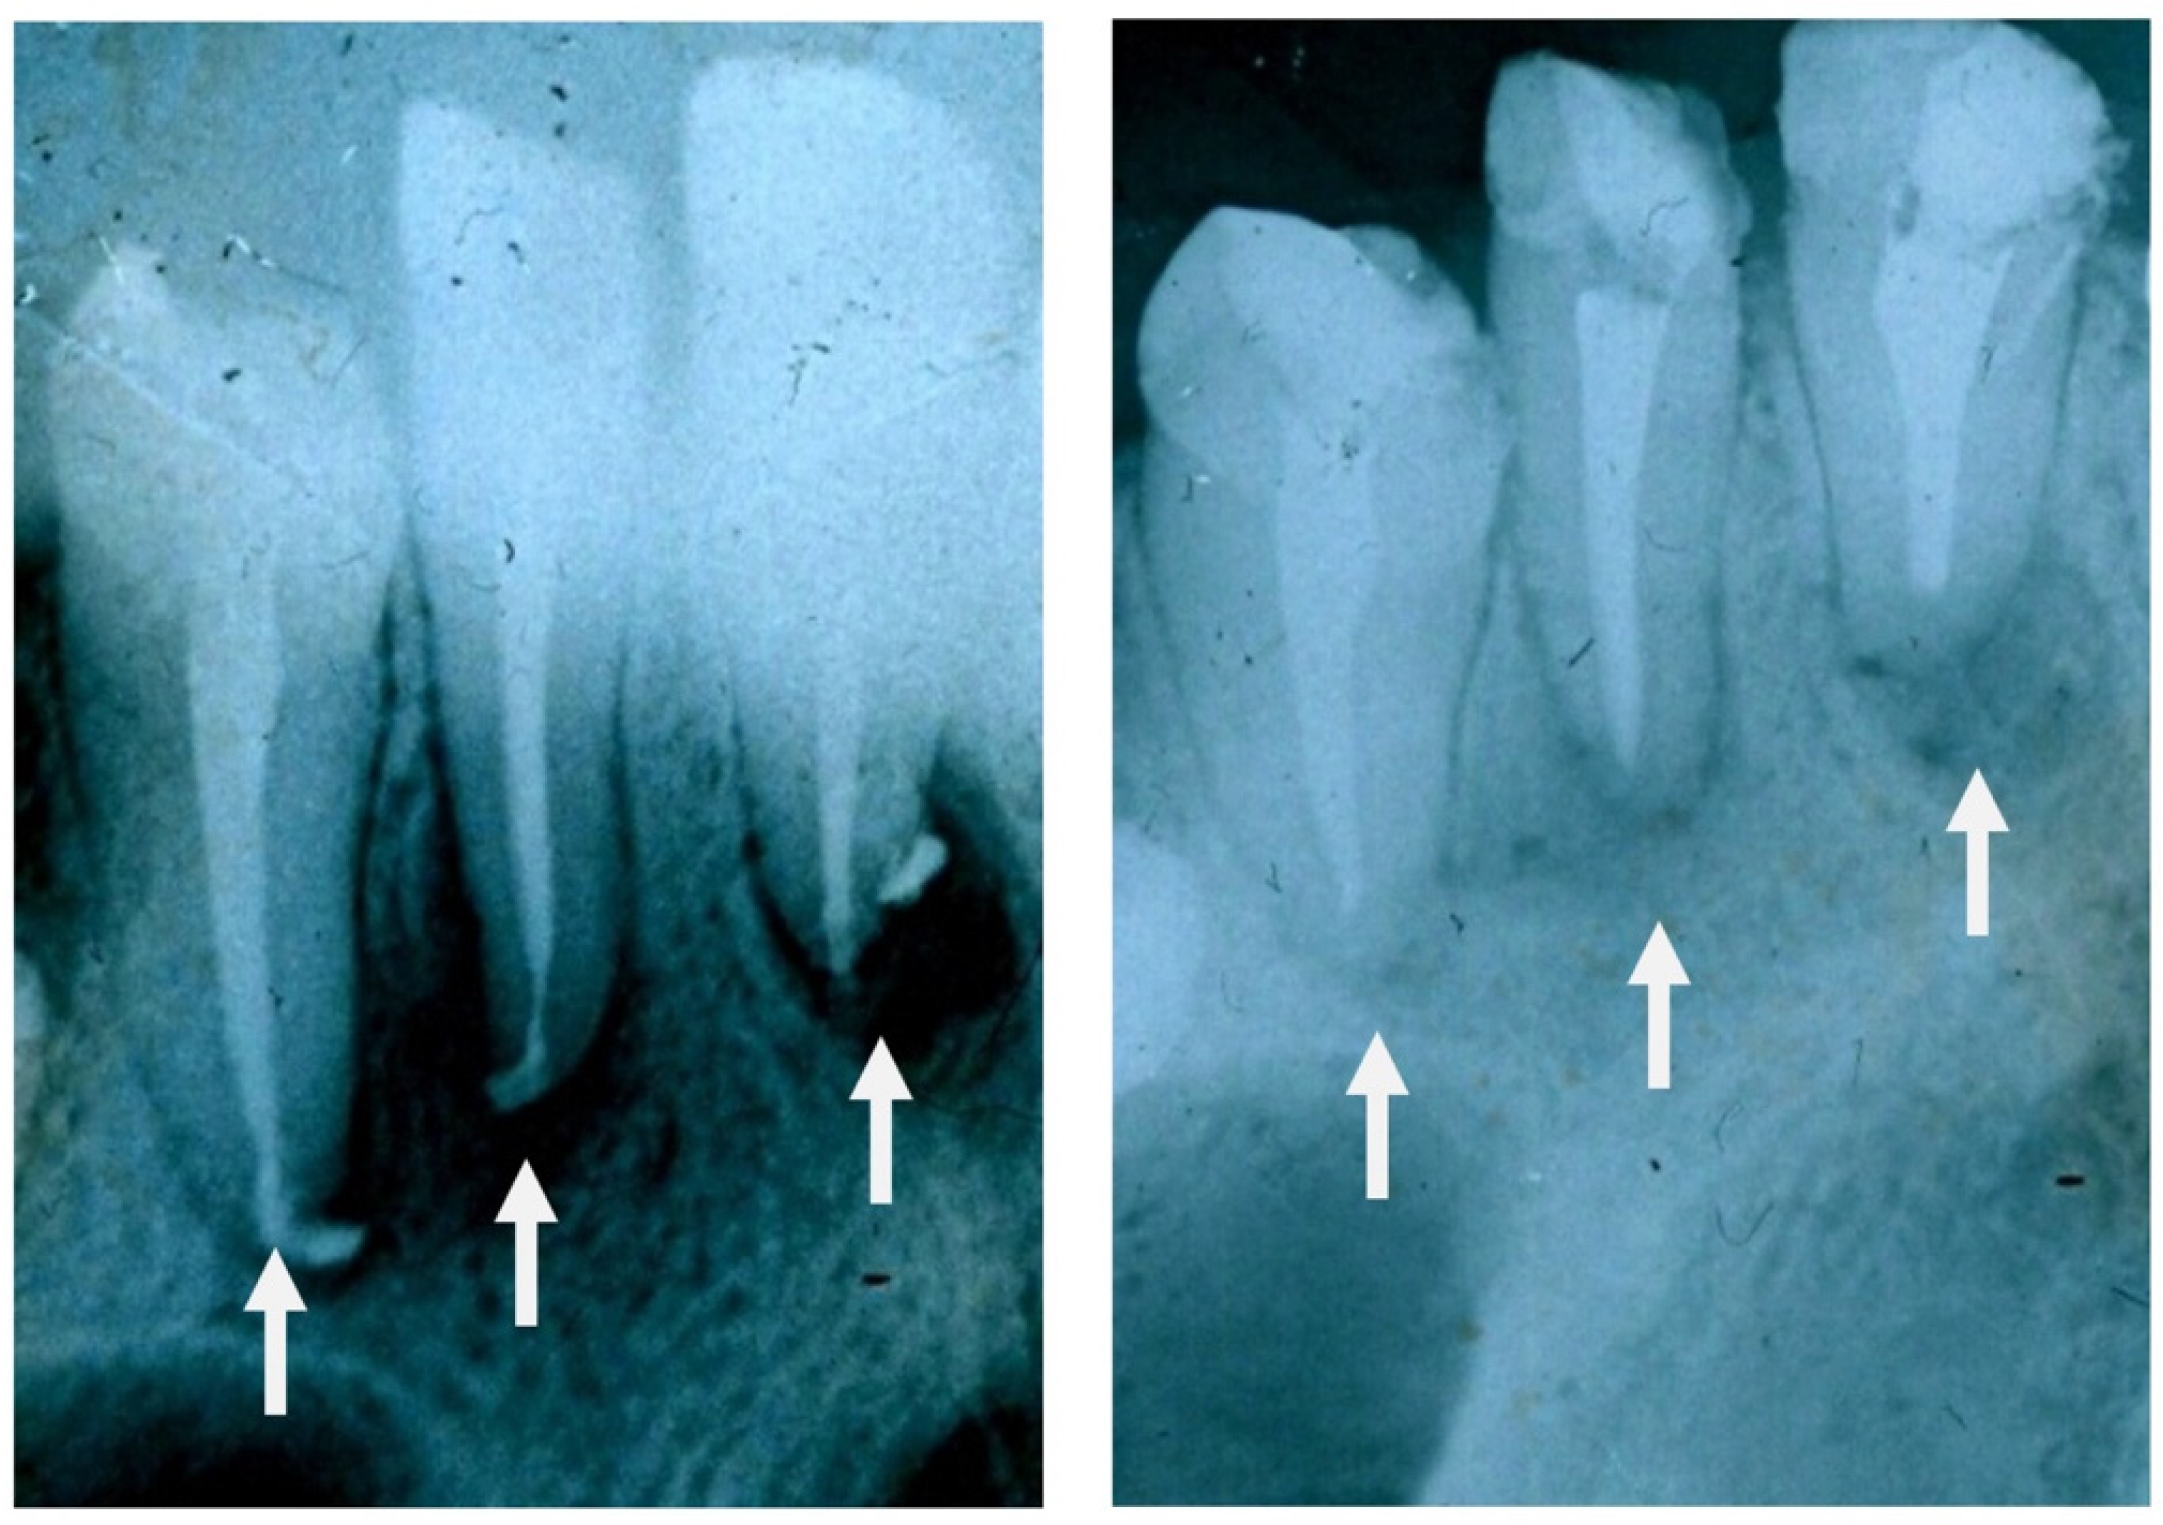

7.1. GC Dental Implants